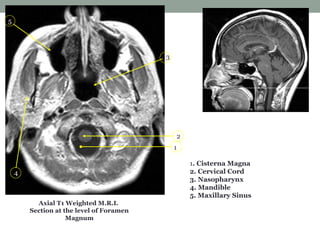

Axial T1 Weighted M.R.I.

Section at the level of Foramen

Magnum

1. Cisterna Magna

2. Cervical Cord

3. Nasopharynx

4. Mandible

5. Maxillary Sinus